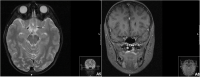

Case presentation: We present 3 particular presentations of LHON. Patient 1 was an 8-year-old boy admitted to the emergency department reporting a progressive bilateral visual loss and intermittent headaches. Neuro-ophthalmological examination revealed a bilateral pseudopapilledema. Lumbar puncture identified intracranial hypertension and the brain and orbits magnetic resonance imaging showed T2 hyperintensity in the posterior region of the left optic nerve and the optic chiasm. Patient 2 was a 12-year-old boy admitted to the emergency department reporting painless, progressive central vision loss in the right eye. Fundus examination revealed a hyperemic disc and vascular network papillary and peripapillary vascular microdilations. Three months later, the left eye presented visual loss. Patient 3 was a 6-year-old female child referred to the neuro-ophthalmology specialist due to painless central visual loss in both eyes. Her BCVA was 1/10 and counting fingers in right and left eye, respectively, and fundus examination revealed a pallor optic disc in the temporal sector.